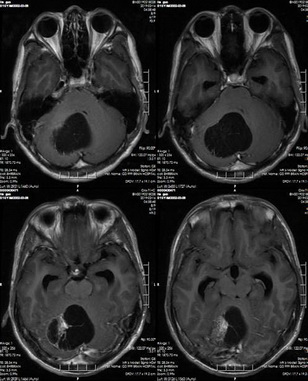

小林,男,16歲,1個(gè)月前無明顯誘因出現(xiàn)頭暈、頭痛,頭痛以枕部最為明顯,有種暈沉感。到當(dāng)?shù)蒯t(yī)院就診,頭部CT及MR提示:右側(cè)小腦囊結(jié)節(jié)性腫塊,醫(yī)生建議到上級(jí)醫(yī)院繼續(xù)治療。7天前,小林出現(xiàn)嘔吐的癥狀,為求進(jìn)一步治療,家屬帶其來到省腦科醫(yī)院。

入院后,神經(jīng)外科醫(yī)生為小林完善相關(guān)檢查,頭部MRI提示:1.右側(cè)小腦半球占位性病變,考慮偏低級(jí)別腫瘤性病變,毛細(xì)胞型星形細(xì)胞瘤可能;2.幕上梗阻性腦積水并腦室旁間質(zhì)水腫;3.小腦扁桃體下疝。

頭部MRI分析

術(shù)前MR示:1.右側(cè)小腦半球占位性病變,考慮偏低級(jí)別腫瘤性病變;2.幕上梗阻性腦積水并腦室旁間質(zhì)水腫;3.小腦扁桃體下疝。